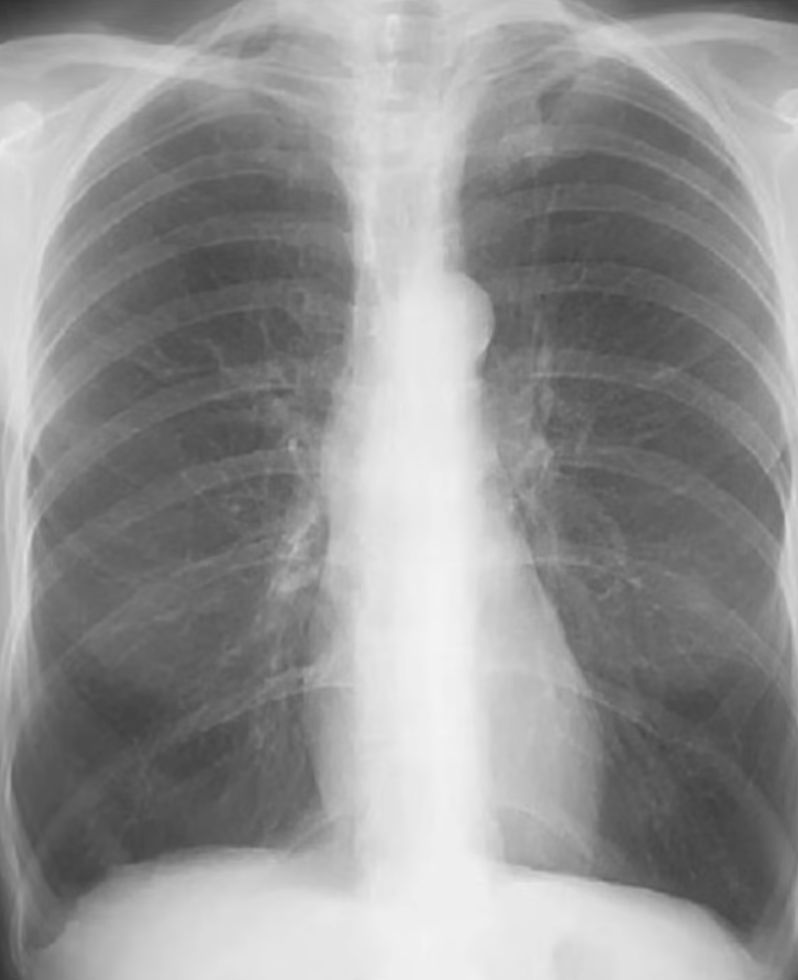

Technical Quality

Rotation

Ensure the patient is not crooked (rotated/slumped to one side). Ensure lung apices are visible above the clavicles. Ensure the vertebral spinous processes bisect the distance between the medial ends of the clavicle.

- The spinous processes will be closer to the clavicle on the side that is rotated forward

Penetration

Considered good when the outlines of the vertebral bodies are visible behind the heart (focus on inter-vertebral spaces).